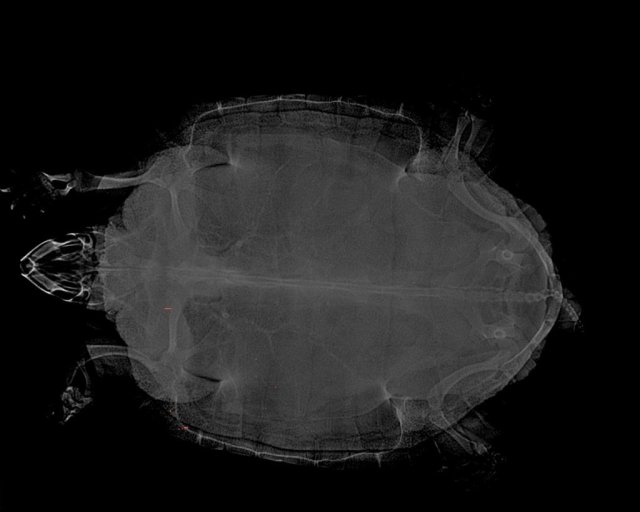

Татьяна.04 Ваше имя: Татьяна Локация: Россия, Люберцы Опубликовано: 7 апреля Автор Опубликовано: 7 апреля Сегодня сделали рентген дополнительно, лучшего качества. Очень надеемся, что черепашечке назначат лечение и она у нас встанет на все 4 лапки. Мне кажется, я чувствую её боль, она такими глазками смотрит, что плакать хочется

Консультанты moth Ваше имя: Мария Локация: Москва Опубликовано: 7 апреля Консультанты Опубликовано: 7 апреля @Татьяна.04 по крайней мере вроде на снимке нет утолщений у суставов, подождём что завтра Мария скажет

Татьяна.04 Ваше имя: Татьяна Локация: Россия, Люберцы Опубликовано: 7 апреля Автор Опубликовано: 7 апреля Да, в ветклинике, где сегодня делали рентген, тоже сказали, что никакого артрита не видать. Уже легче. Но да, без заключения Марии пока ничего не ясно. Очень ждём завтра ?

Татьяна.04 Ваше имя: Татьяна Локация: Россия, Люберцы Опубликовано: 29 апреля Автор Опубликовано: 29 апреля Сделали все возможные анализы и КТ и вот заключение: -признаки вывиха левой плечевой кости со смещением, дегенеративными изменениями, краевого остеопороза и частичного лизиса прилегающих костей пояса грудной конечности Диф. диагноз остеомиелит, признаки артрита левого плечевого сустава с вовлечением окружающих тканей (мышцы, мягкие ткани) в патологический процесс. Лечимся у Бойцовой Марии, очень надеемся, что получится сохранить лапку черепахе. Мария - замечательный врач и чудесный человек. С огромным понимаем относится к нашей ситуации и делает всё возможное, чтобы наша черепашка поправилась. Огромное СПАСИБО, что порекомендовали к ней обратиться. Будем бороться дальше